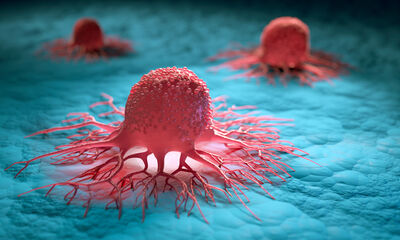

Le général de Gaulle et Albert Einstein ont tous deux été terrassés par une rupture d’anévrisme de l’aorte abdominale. « J’ai mal au dos », aurait dit l’ancien président avant de s’écrouler. L’anévrisme est une dilatation de l’aorte, grosse artère située sous le rein. Il progresse de nombreuses années, ce qui fragilise les parois de l’artère. Et à l’image d’un ballon de baudruche trop gonflé, l’aorte peut éclater. Un accident qui arrive sans crier gare et tue entre 80 et 90 % des victimes. En 2011, 1 500 personnes en sont décédées.

L’anévrisme de l’aorte abdominale menace surtout les hommes (13 hommes pour 1 femme), après 65 ans, les fumeurs et ceux ayant des antécédents familiaux. La pathologie est généralement découverte par hasard ou trop tard lorsque l’anévrisme se rompt. Or, il est possible d’agir chirurgicalement pour éviter la rupture. « Ces interventions sont complexes, mais le risque opératoire est faible, souligne la Pr Gabrielle Sarlon, médecin vasculaire au CHU de Marseille. Et la détection d’un anévrisme est aussi l’occasion d’inciter le patient à arrêter de fumer, à traiter une éventuelle hypertension, un diabète… ce qui permet de stabiliser l’anévrisme. »